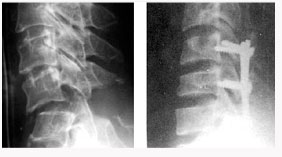

척추관 협착증의 방사선 소견

후외방 유합술(Posterlateral fusion) : 광범위한 후방 감압술 후 척추 외측에 있는 후관절과 횡돌기 간의 유합을 얻는 것.

- 충분한 감압을 얻을 수 있다.

- 신경 손상의 위험이 적다